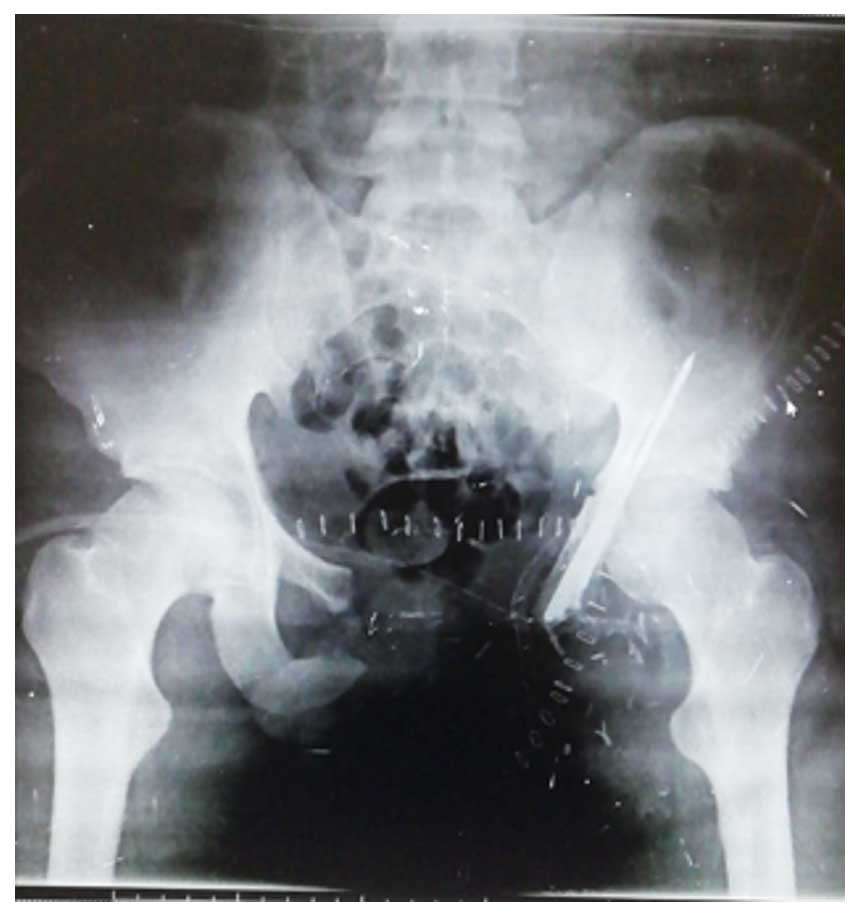

Ameliyat Öncesi: Röntgende pubik koldan kaynaklanan düzensiz sınırlı ve içerikli kıkırdak doku tümörü görülmekte.